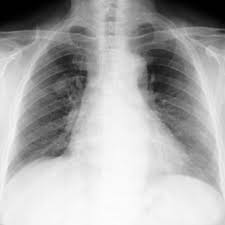

That same fungal infection is often frequently mistaken for squamous cell carcinoma, or skin cancer, when it shows up on the skin. Sarcoidosis is a rare disease caused by inflammation. It usually occurs in the lungs and lymph nodes, but it can occur in almost any organ. Only 10 similar cases had been reported previously. When sarcoidosis affects the lungs, symptoms can mimic idiopathic pulmonary fibrosis including shortness of breath and a dry cough. No prior imaging was available for comparison. After some conversations and research i now know sarcoidosis can be mistaken for cancer. A condition called sarcoidosis, most commonly found in the lungs, can be mistaken for cancer, tuberculosis, or other infections, as its symptoms are similar. That time between when they tell you the possibilities and when you get the results from the biopsy is terrifying. Occasionally this pattern of fibrocystic change is seen in the lower lung zones, an atypical location that may cause pulmonary sarcoidosis to be mistaken for. Which was a flare up of sarcoidosis. A permanent pathological slide, however, indicated that right interlobar (#11s) lymph nodes involved both sarcoidosis and lung cancer metastasis. Can sarcoidosis turn into cancer.

No prior imaging was available for comparison. The cancers in particular are lung cancer, malignant lymphomas, and cancer in other organs known to be. I've been going to support groups for the disease for 20 years now and find 3 or 4 patients a year who are diagnosed initially as having lung cancer. Furthermore, lung cancer symptoms, such as a persistent cough, back pain or weight loss, can resemble a cold or bronchitis and may not raise suspicions of lung cancer, herrera adds. Researchers emphasize that clinicians should be aware of systemic sarcoidosis because it can easily be mistaken for cancer progression.